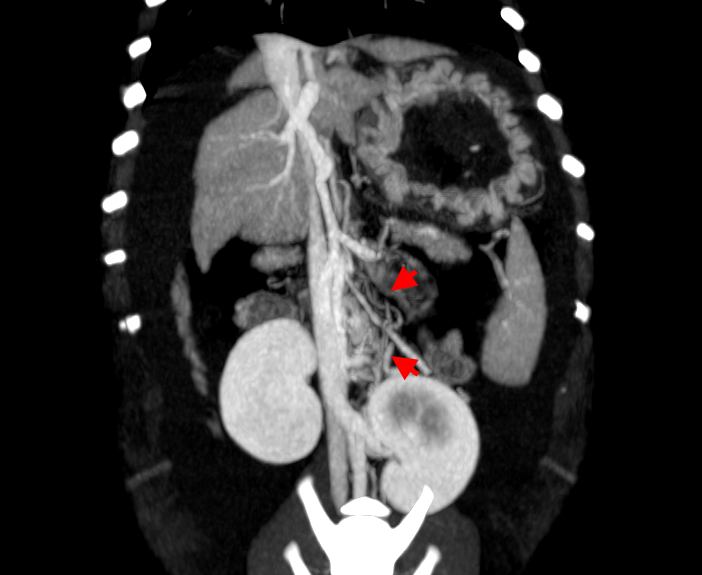

АВМ печени принято делить на правосторонние и левосторонние. Последние подразделяются на левую латеральную и медиальную мальформации в зависимости от положения выносящей вены (рис. 2).

Диагностика печеночных АВМ осуществляется с применением КТ-ангиографии, выявляющей сосудистую сеть (или «гнездо»), образованную ветвями приносящей печеночной, гастродуоденальной, левой желудочной и другими артериями, через которую происходит слияние с воротной веной (рис. 3). Артериальная фаза является самой важной в идентификации приносящих ветвей артериовенозной мальформации. АВМ имеют тенденцию изменяться со временем, в связи с этим КТ-ангиографию рекомендуют проводить как можно ближе к дате планируемого хирургического вмешательства.